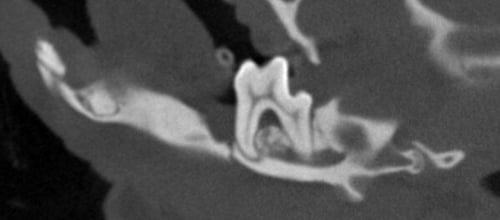

Above: CT slice with insufficient bone to be able to repair

Coley Kay is severely brachycephalic and already had an almost ‘flat face.’ The fractures were present at the mid to caudal mandible at each lower first molar.